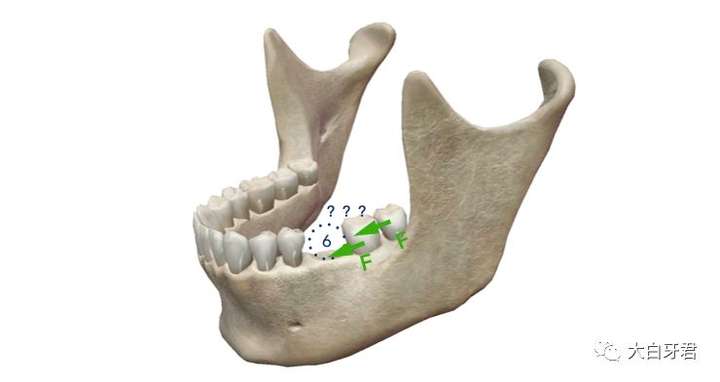

再比如缺失某些单独的特定牙齿,口腔医生可以通过正畸的治疗方法,把缺失牙齿两侧的牙齿拉拢,从而消除空隙,让牙列「完整」。再加上如果本身病人的牙齿就比较拥挤或者有其他适合做牙齿矫正的指证,就可以通过这种方案来修复空隙,达到「缺牙不补」的目标。甚至,我们还可以把余留的智齿作为「有用」的牙齿往前移动,来弥补缺失的牙齿。

有些牙齿缺失,依靠正畸使自身牙齿的移动来修复缺隙,无需镶牙

但是,通过矫正牙齿的方案来修复缺隙,有一定局限性,并不是所有情况都通用。而且,除了较贵的费用之外还存在时间成本,往往完成正畸治疗并且把空隙都消除,需要两年、三年甚至更久的时间。

最后,还可以使用自体牙齿再植技术,在缺失的牙齿拔除后的即刻,把其他位置的智齿(往往是恰好需要拔掉的智齿)完整拔除、 迅速移植到缺牙处,这个牙齿会在未来的一段时间内逐渐牢固,发挥余热。

同样的6号牙缺失,条件合适的话,可以使用上面的8号牙(智齿)拔除后即刻再植到缺失的位置,无需镶牙。

当然,这种方案同样有局限性,不是所有的情况都可以适用。